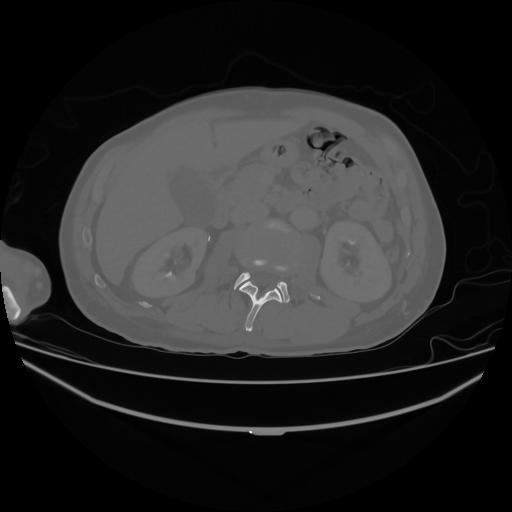

5 CUERPO,CE,Vol,1.0,CUERPO,,